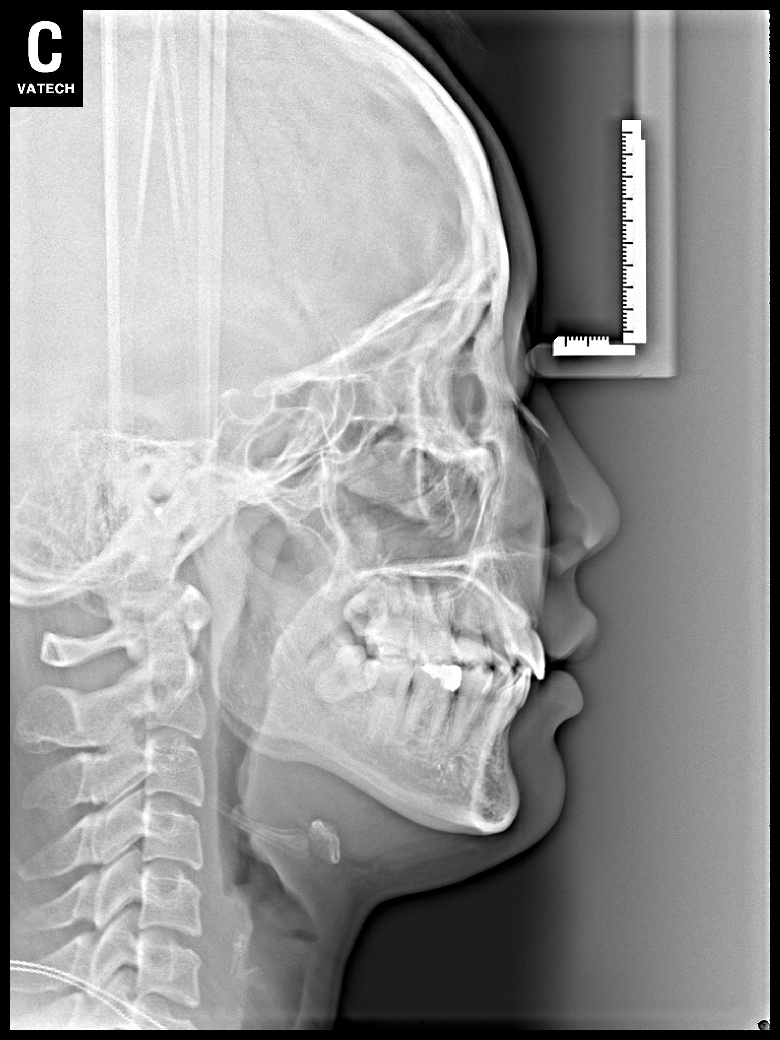

치료 전 사진입니다.